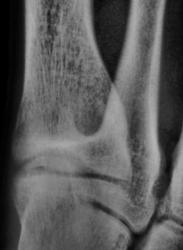

Кстати, у него - же, на мой взгляд, косто-хрящевой экзостоз по тылу таранной кости.

Кстати, у этого-же пациента, костный экзостоз в области проксимального эпиметафиза 2 плюсневой кости.